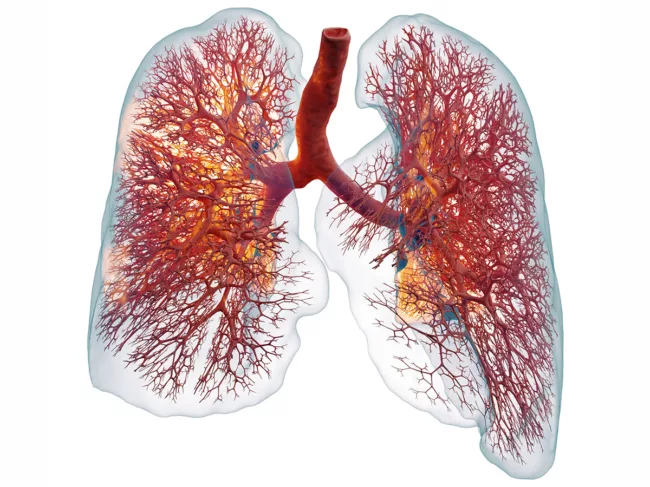

Ebenbuild technology lung with ARDS

Ebenbuild aims to transform lung care with digital twin tech

Ebenbuild GmbH is hoping that its digital twin technology platform that combines AI and physics-based computational models tailored to individual patients will transform respiratory care. From drug development to optimizing mechanical ventilation in critical care, the company’s software-based solutions aim to reveal what is happening in the ‘black box’ of the lungs, helping clinicians to improve outcomes and reduce mortality. Read More